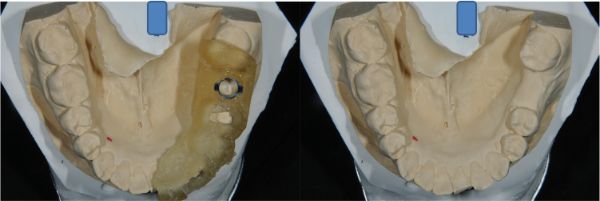

3 Shape植牙設計

電腦手術模板

上咬合器製作模型

咬合器製作假牙